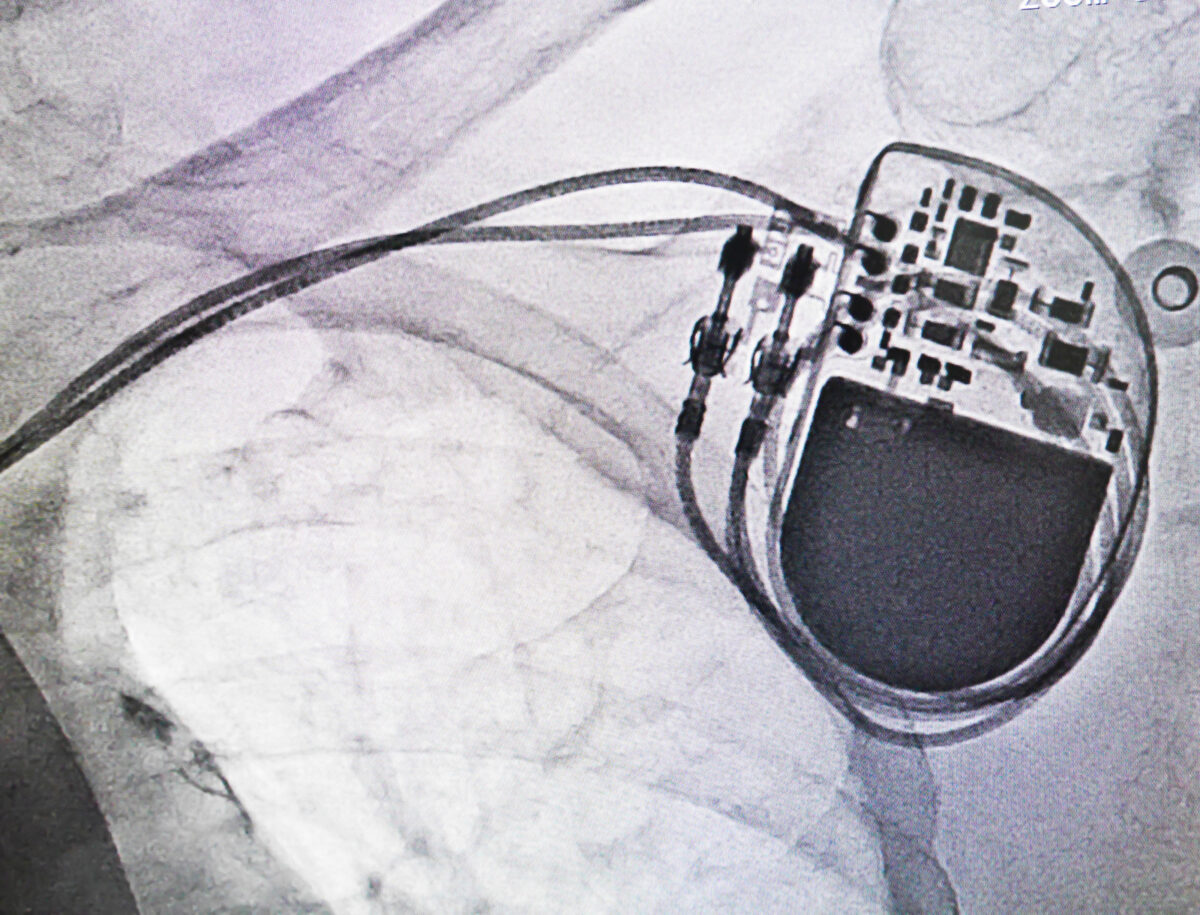

Pacemaker and TENS Unit Use Is it Safe? Roots of Being Using A Tens Unit With A Pacemaker The authors suggest that tens is contraindicated in synchronous pacemakers but tens can be given without risk to those with asynchronous pacemakers. Here are things you should do when using tens units. The tens unit (dynex ii) was connected to the patient in standard treatment fashion in four areas: Transcutaneous electrical nerve stimulation (tens) this procedure uses electrical signals to. Using A Tens Unit With A Pacemaker.